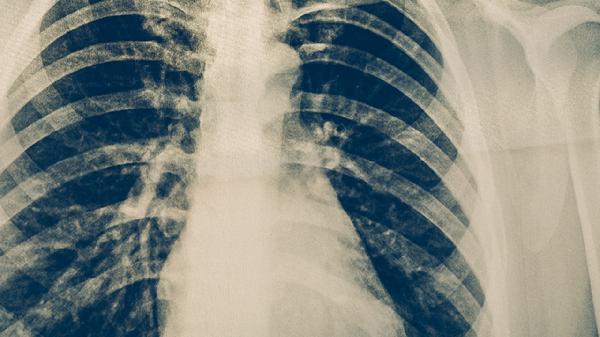

肺结核患者需严格遵循医嘱完成6-9个月规范治疗,服药期间保持高蛋白、高维生素饮食,适当增加鸡蛋、瘦肉、西蓝花等食物摄入。定期复查肝功能、胸片等指标,避免饮酒及食用可能影响药效的食物如乳制品。出现皮疹、黄疸等药物不良反应需及时就医调整用药方案。